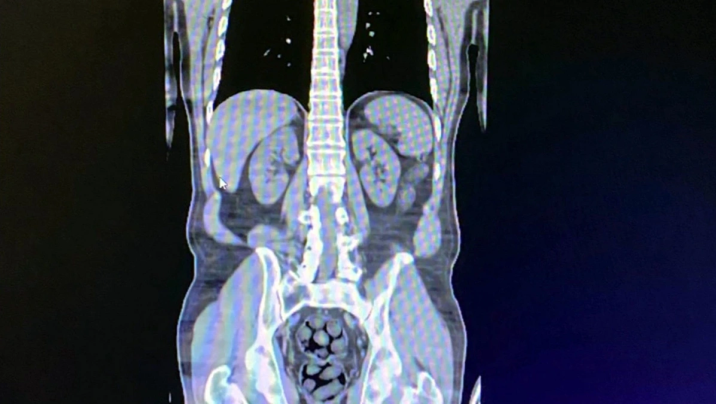

Stopnarkotik.az "Haber Global"a istinadən xəbər verir ki, şübhəlilərin daxili orqanlarından 91 paketdə 1 kilo 126 qram metamfetamin çıxarılıb.